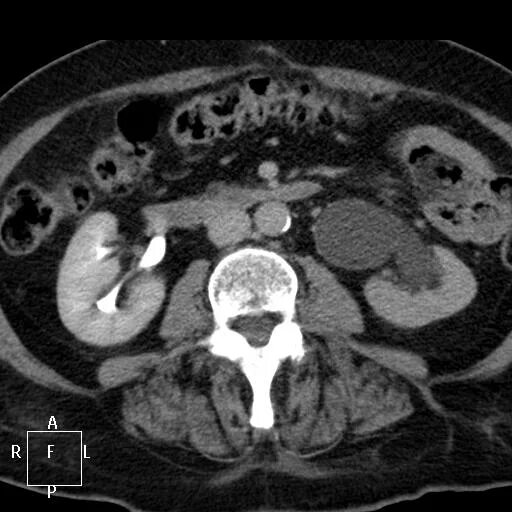

Рак прямой кт